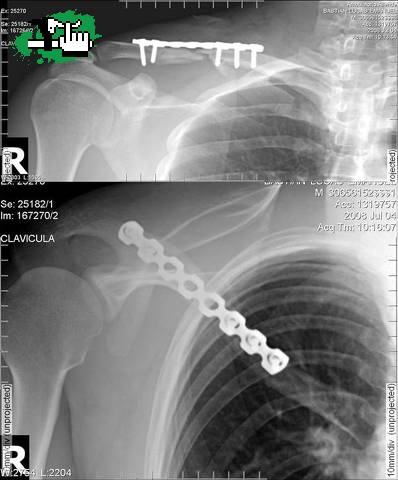

Bue aca van dos radiografias de lucas de su clavicula alivianada echo, jaja ya por suerte esta en la casa un abraso para todos Luisitosss